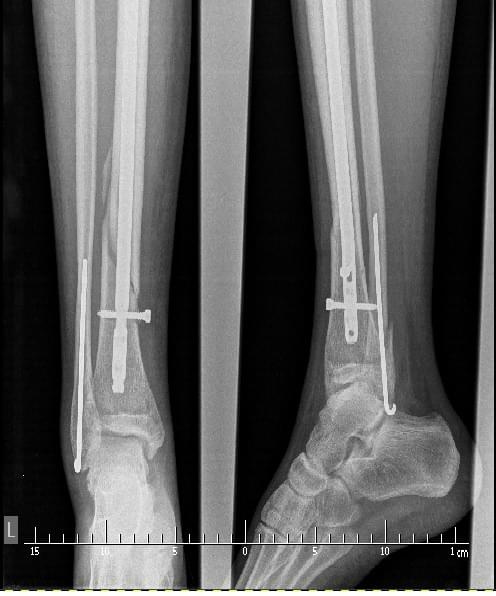

Jak wygląda zrost na tym etapie i co czeka mnie po wyjęciu śrubek?

Witam, 12 grudnia złamałem kość piszczelową, strzałkową w 1/3 dalszej z przemieszczeniem oraz kostkę boczną z przemieszczeniem. Piszczel zespolony gwoździem śródszpikowym blokowanym a kostka prętem rusha. Po operacji noga usztywniona szyną zaś po 6 tyg zamieniona na orteze. W połowie... Witam, 12 grudnia złamałem kość piszczelową, strzałkową w 1/3 dalszej z przemieszczeniem oraz kostkę boczną z przemieszczeniem. Piszczel zespolony gwoździem śródszpikowym blokowanym a kostka prętem rusha. Po operacji noga usztywniona szyną zaś po 6 tyg zamieniona na orteze. W połowie lutego czeka mnie dynamizacja zespolenia. Jak wygląda zrost na tym etapie i co czeka mnie po wyjęciu śrubek? Mniej więcej kiedy stanę w pełni na nogi? https://images83.fotosik.pl/331/bf7e4615b6a9e430gen.jpg po 6tyg